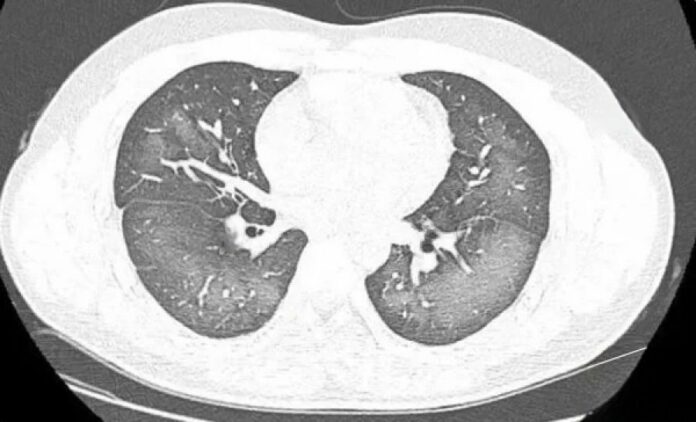

他赶紧前往湖南省长沙市第三医院就诊。在进行肺部CT检查时,医生惊讶地发现李林的双肺出现了广泛的白色病变,检查报告甚至显示了“白肺”。

据了解,“白肺”通常指的是在X光或CT检查中显示出的重度肺部炎症。患者的肺部会呈现大片白色病变,常伴随呼吸困难和呼吸衰竭,极端情况下可能导致其他器官功能障碍。

长沙市第三医院放射影像科医生指出,“白肺”的成因除了感染和弥漫性肺泡出血综合症等,吸入有害物质如粉尘、喷雾等也可能导致肺部出现广泛的白色病变。